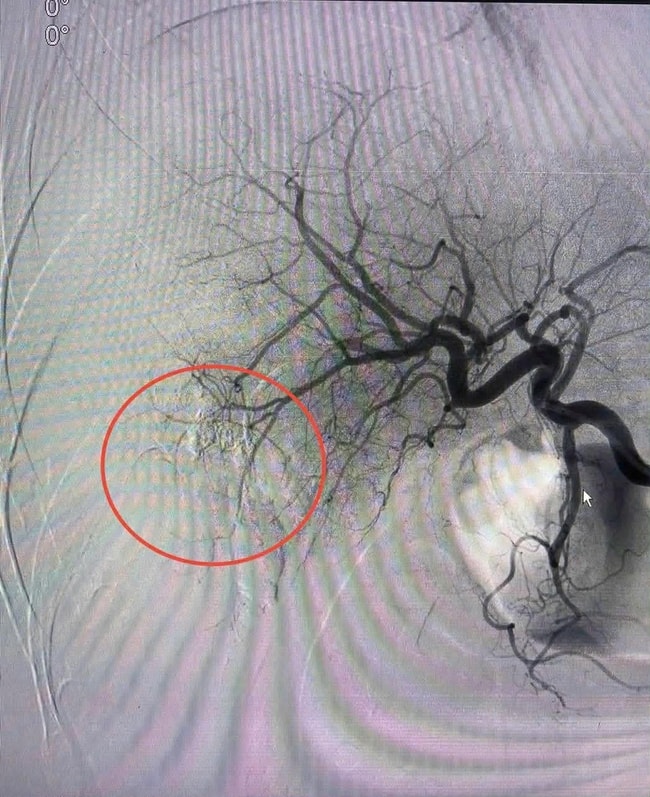

Bác sĩ Nguyễn Đức Hùng- Trưởng khoa Chẩn đoán hình ảnh và Điện quang can thiệp, người trực tiếp thực hiện ca can thiệp, cùng ekip đã tiến hành luồn vi ống thông từ động mạch đùi đến vị trí động mạch gan đang chảy máu. Dưới màn hình tăng sáng, các bác sĩ đã bơm vật liệu gây tắc mạch để bít hoàn toàn điểm vỡ.

Chỉ sau 20 phút vừa hồi sức tích cực vừa can thiệp, vị trí chảy máu đã được kiểm soát hoàn toàn. Huyết áp của bệnh nhân dần trở lại bình thường, các chỉ số sinh tồn ổn định, chính thức thoát khỏi tình trạng sốc nguy kịch.